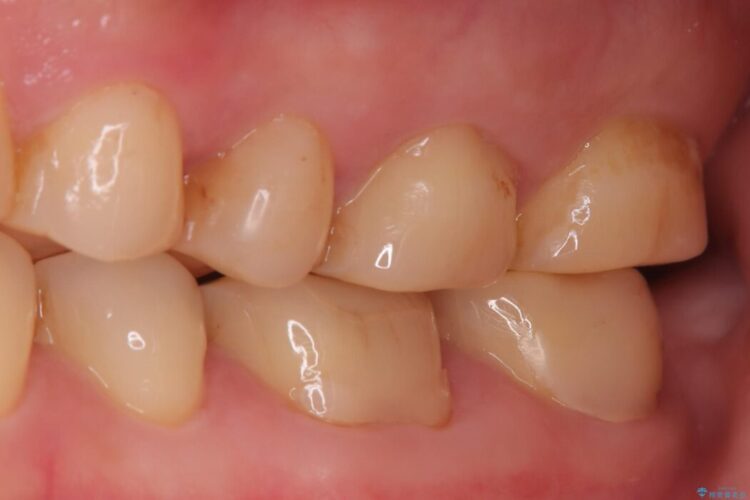

欠けた奥歯をPGAで補強。違和感のない咬み心地へ

欠けた奥歯をPGAで補強。違和感のない咬み心地へ ビフォー 欠けた奥歯をPGAで補強。違和感のない咬み心地へ アフター

以前治療した奥歯(右下7番)の詰め物が欠けてしまったとご来院された患者様です。